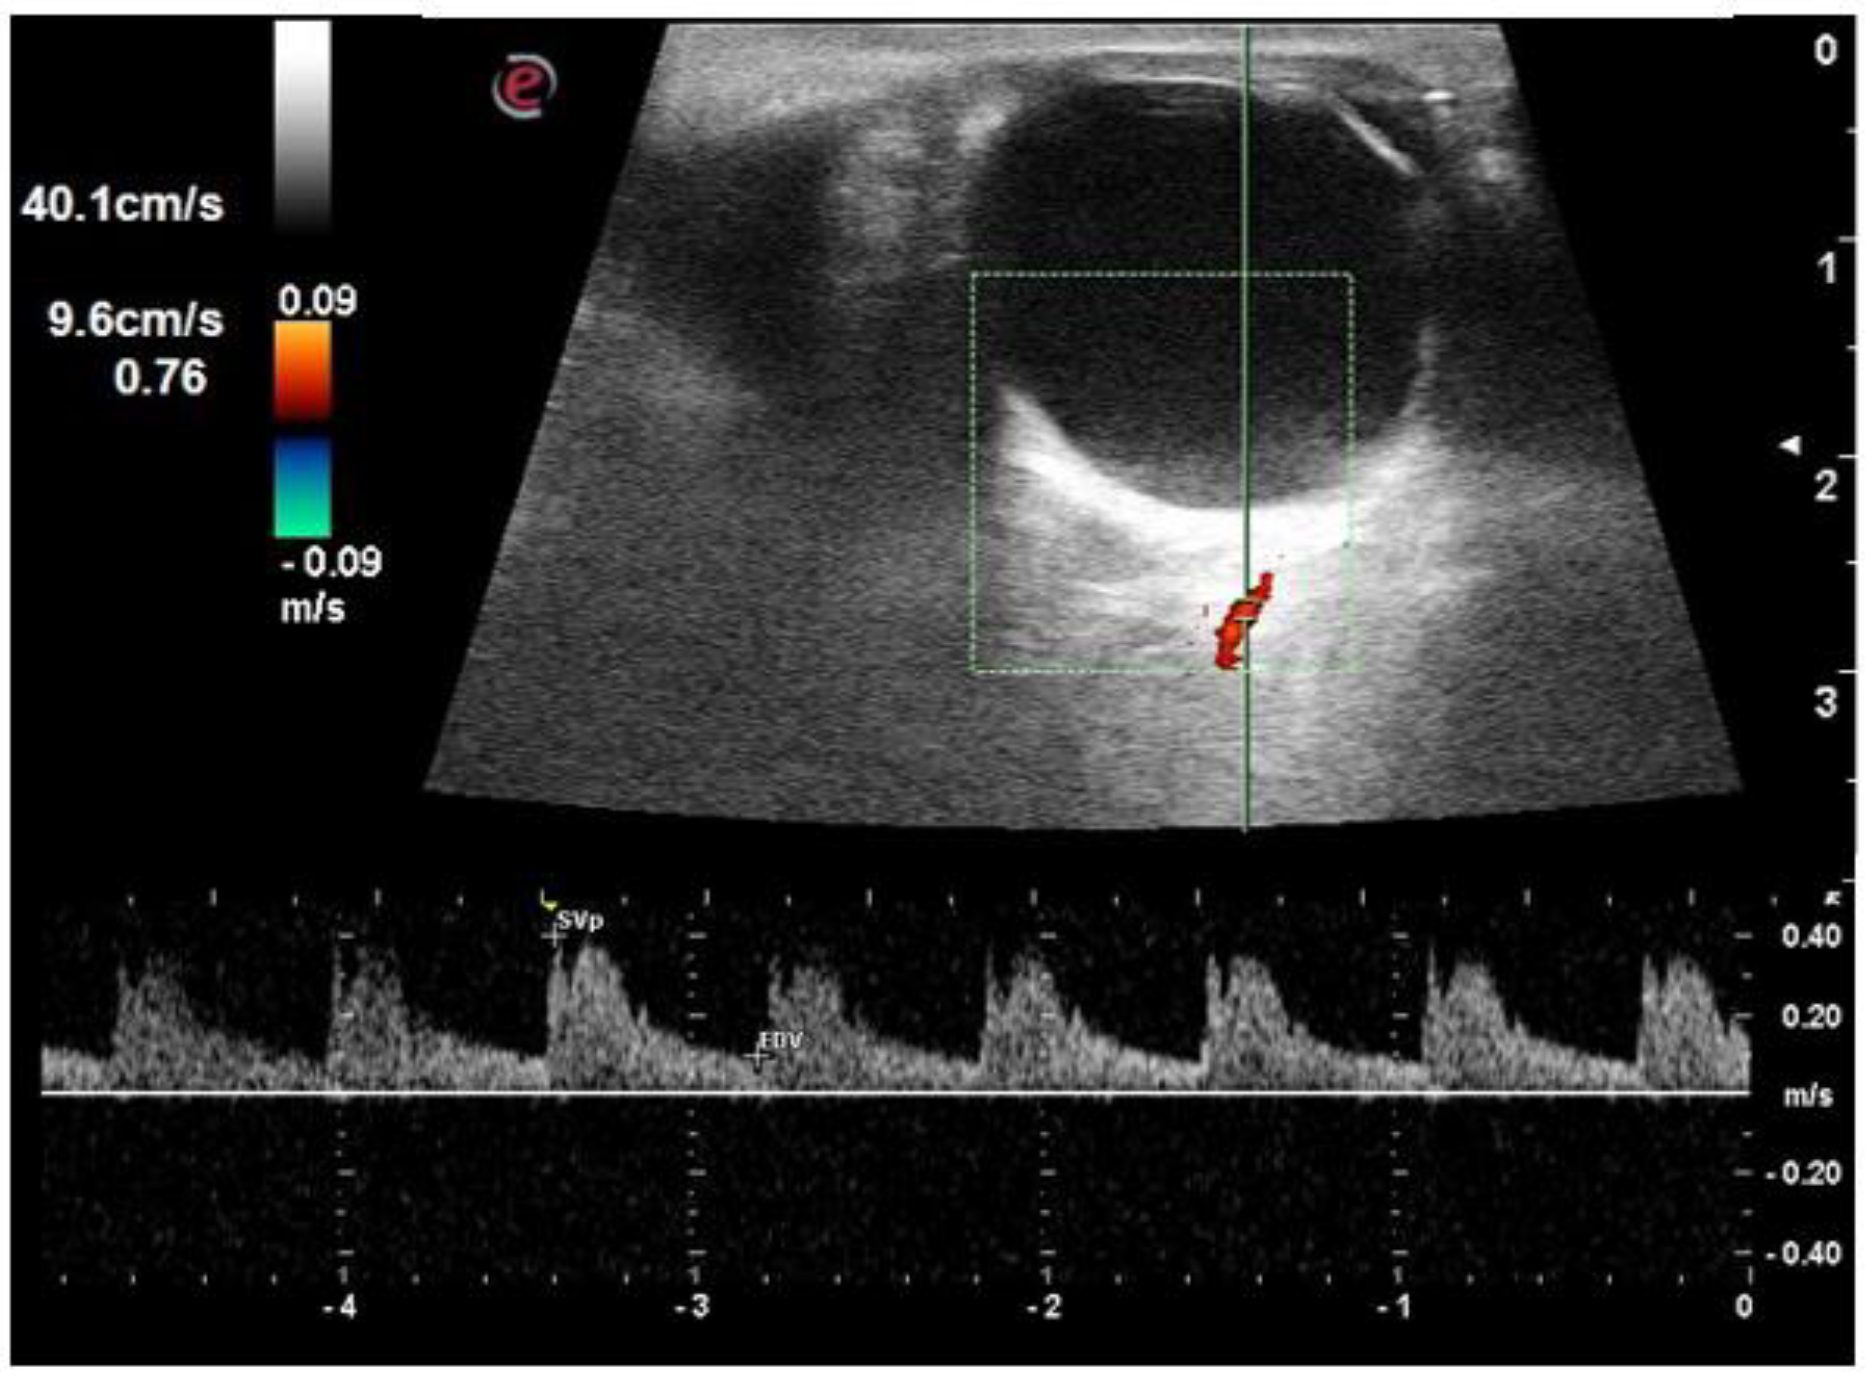

| PSV of ophthalmic artery (cm/s) | 31.9 ± 2.6 | 32.7 ± 3.0 | 33.8 ± 3.8 | 0.550 |

| EDV of ophthalmic artery (cm/s) | 8.7 ± 0.9 | 8.8 ± 1.6 | 8.3 ± 1.3 | 0.240 |

| RI of ophthalmic artery | 0.72 ± 0.02 | 0.73 ± 0.03 | 0.75 ± 0.03 | <0.001 |

| PSV of central retinal artery (cm/s) | 16.1 ± 1.9 | 15.8 ± 3.1 | 14.2 ± 2.7 | 0.010 |

| EDV of central retinal artery (cm/s) | 5.1 ± 0.7 | 4.8 ± 1.1 | 3.9 ± 1.0 | <0.001 |

| RI of central retinal artery | 0.68 ± 0.03 | 0.69 ± 0.03 | 0.72 ± 0.04 | <0.001 |